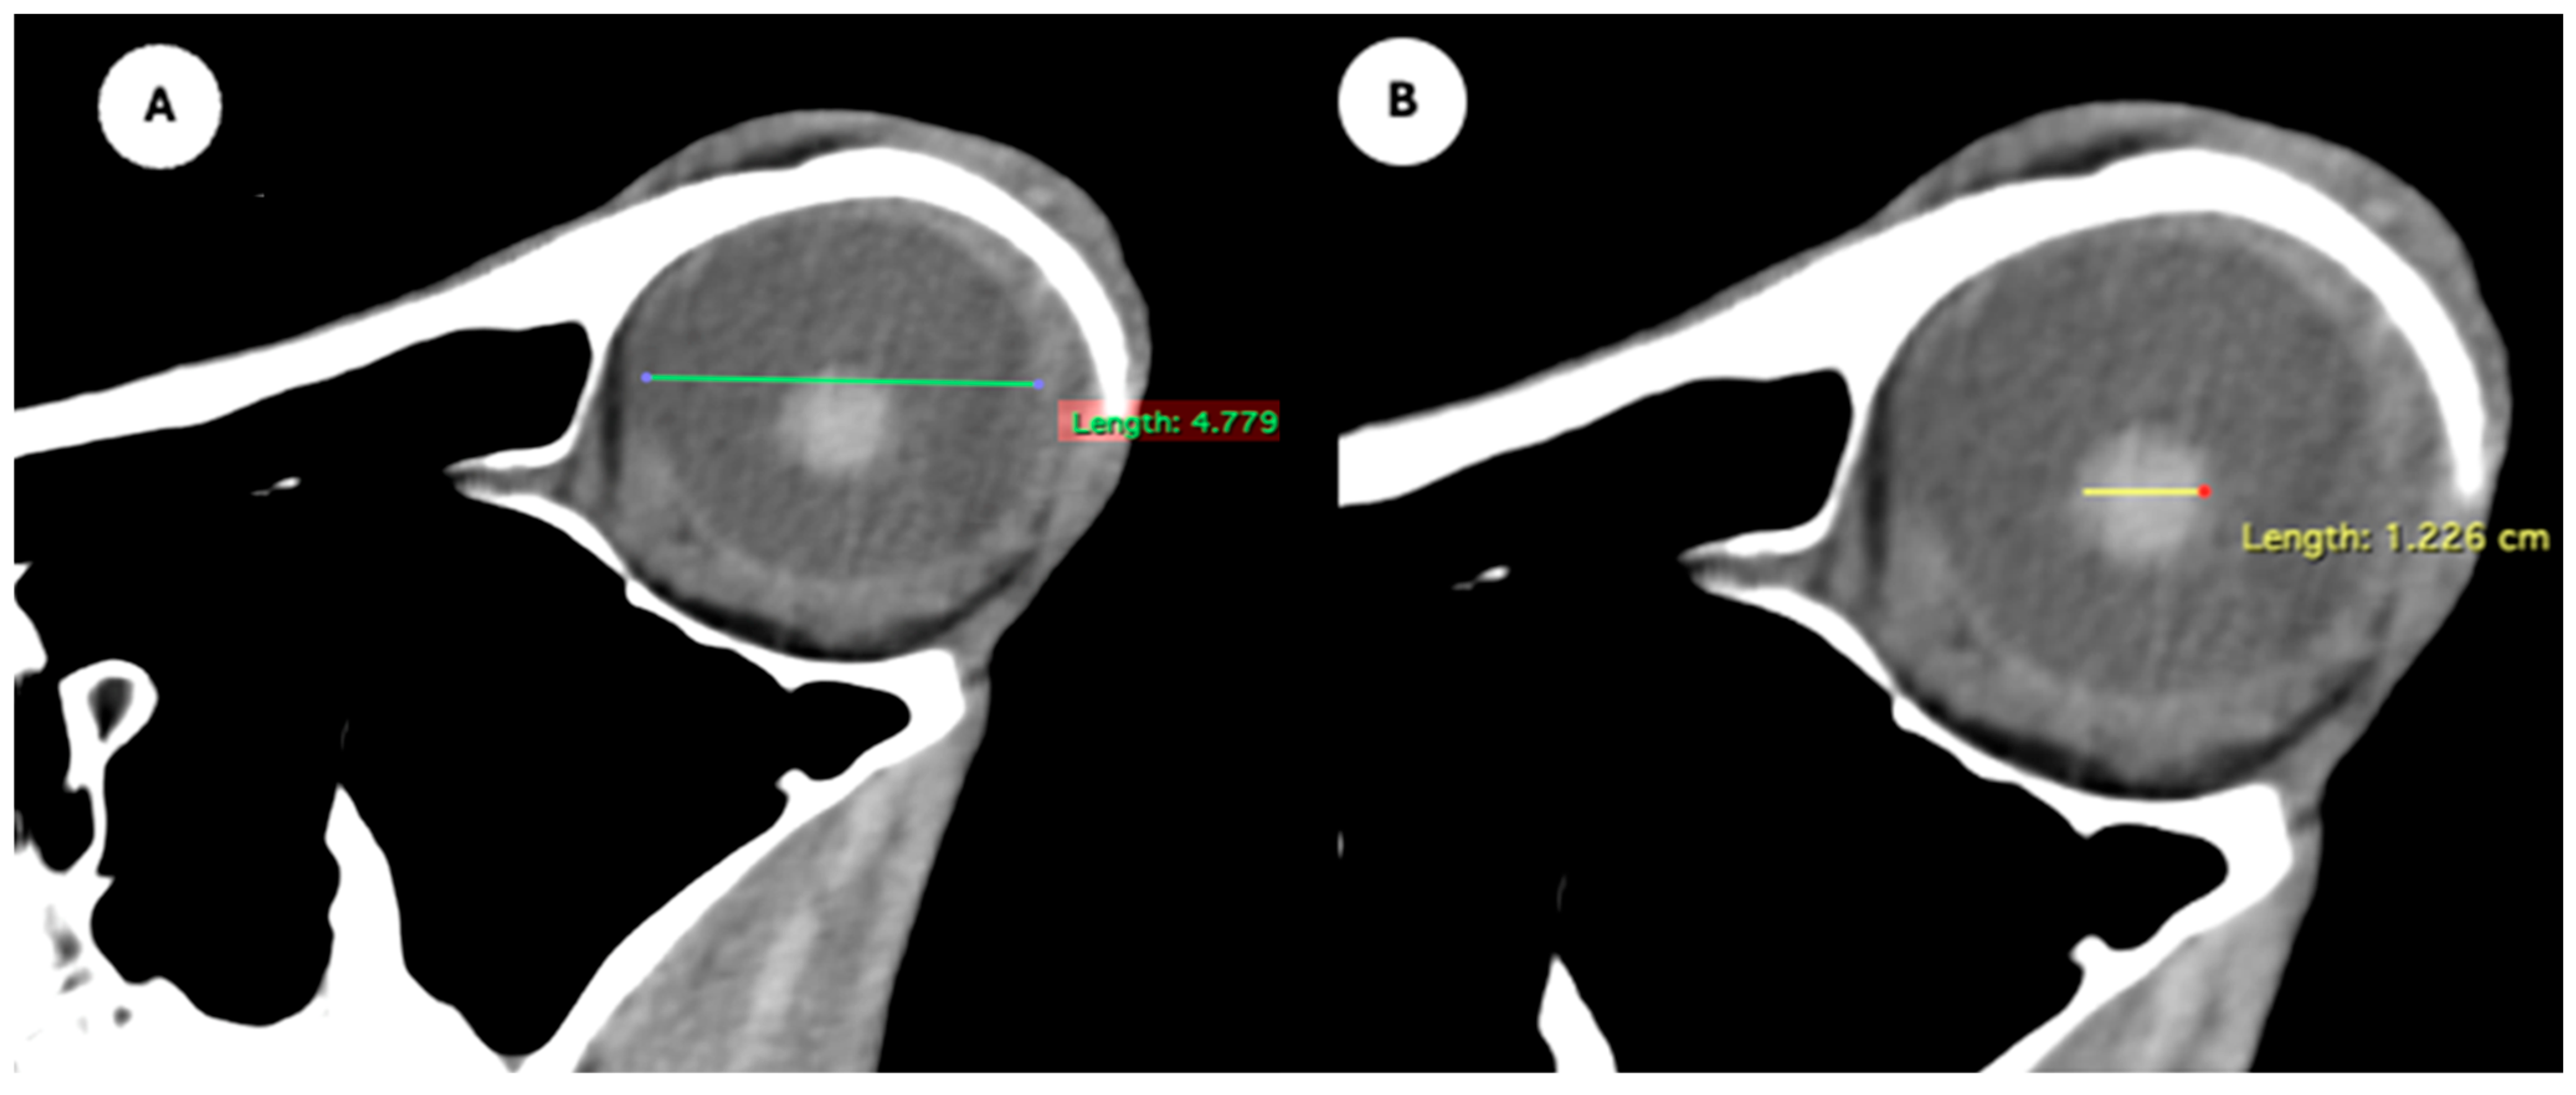

Figure 1. (A) Transverse multiplanar reconstruction (MPR) of the equine eyeball showing the maximum anterior–posterior distance (axial length), measured from the external surface of the cornea to the internal surface of choroid/retina/sclera, and the maximum latero-medial distance (equatorial width), measured perpendicular to the axial length. (B) Transverse MPR illustrating lens dimensions, with the latero-medial distance (equatorial width), measured at its widest point.

Figure 2. Dorsal multiplanar reconstruction (MPR) images showing (A) the maximal latero-medial distance of the lens and (B) the maximal latero-medial distance of the eyeball, measured perpendicular to the axial length, immediately caudal to the lens. - Orbital cavity height: Maximal dorsoventral distance of the orbital cavity at the level of the eyeball.

Table 1 provides summary statistics (mean, median, range, and standard deviation) for the internal ocular measurements of the left eye, right eye, and both eyes combined across all 20 horses. The average ocular measurements indicated that the eyeball height (5.19 ± 0.13 cm) was greater than its width (4.28 ± 0.12 cm), confirming the characteristic oval shape of the equine eye. The mean axial length was 5.09 ± 0.17 cm, consistent with previous descriptions of large-globe morphology in horses. The orbital cavity measured 5.27 ± 0.12 cm in height and 6.29 ± 0.14 cm in length. The anterior and posterior chambers had mean widths of 0.56 ± 0.07 cm and 2.26 ± 0.09 cm, respectively. The lens exhibited a mean height of 1.53 ± 0.06 cm, width of 1.23 ± 0.06 cm, and length of 1.63 ± 0.04 cm. These results collectively reflect the regular proportions and bilateral symmetry of the equine eyeball and its internal structures, as detailed in Table 1. The Mann–Whitney U test revealed no statistically significant differences in the measurements between the right and left eyes. Similarly, when all variables were considered collectively, the analysis confirmed the absence of significant differences between both eyes